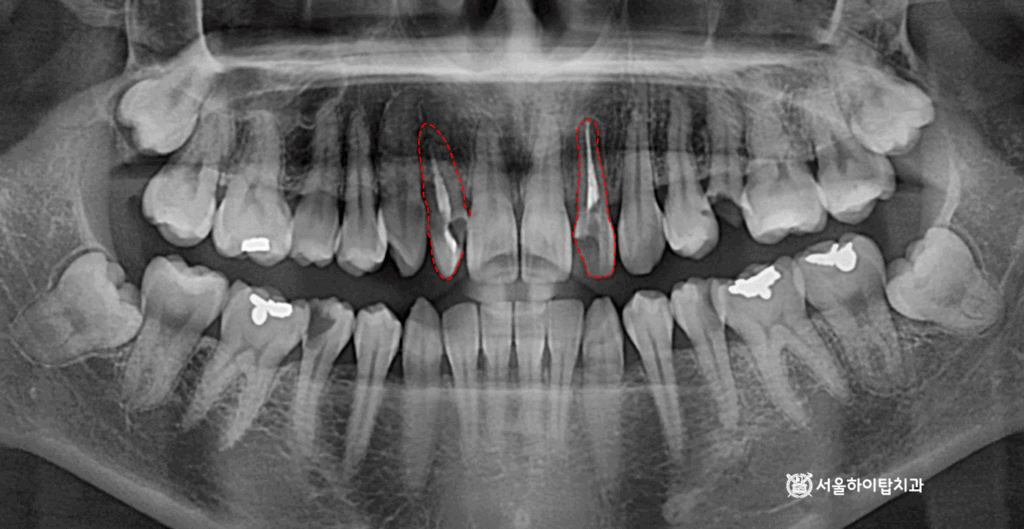

1. 초진

초진 파노라마 엑스레이입니다.

주안역 치과 에서 표시해 둔 부분을 보면,

신경치료를 받은 상태임을 알 수 있습니다.

또한 치아의 머리, 즉 치관 부분을 보면

구조가 작아진 형태를 관찰할 수 있는데,

이는 과거 보철 수복을 위해

형태를 다듬는 프렙(prep)

과정을 거쳤기 때문입니다.

다시 말해, 현재는

수복용 크라운이 없는 상태로,

치아 본래 구조가 이미 손상된

상태라는 것을 알 수 있습니다.